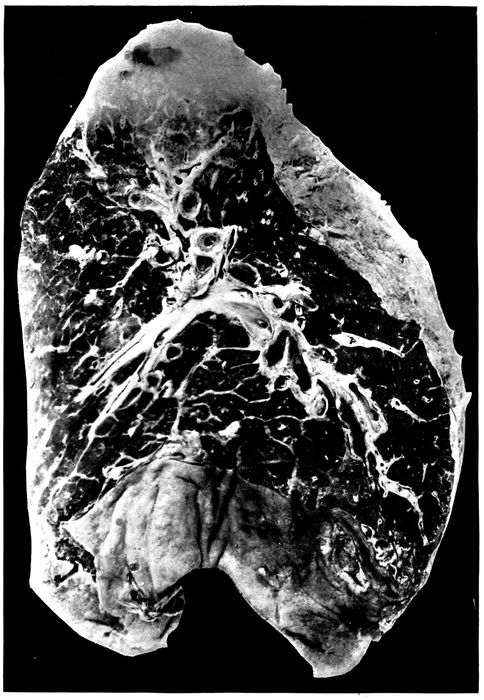

25. Advanced bronchiectasis throughout lower left lobe 258

26. Unresolved bronchopneumonia with tubercle-like nodules of peribronchiolar consolidation best seen in lower lobe; bronchiectasis 268